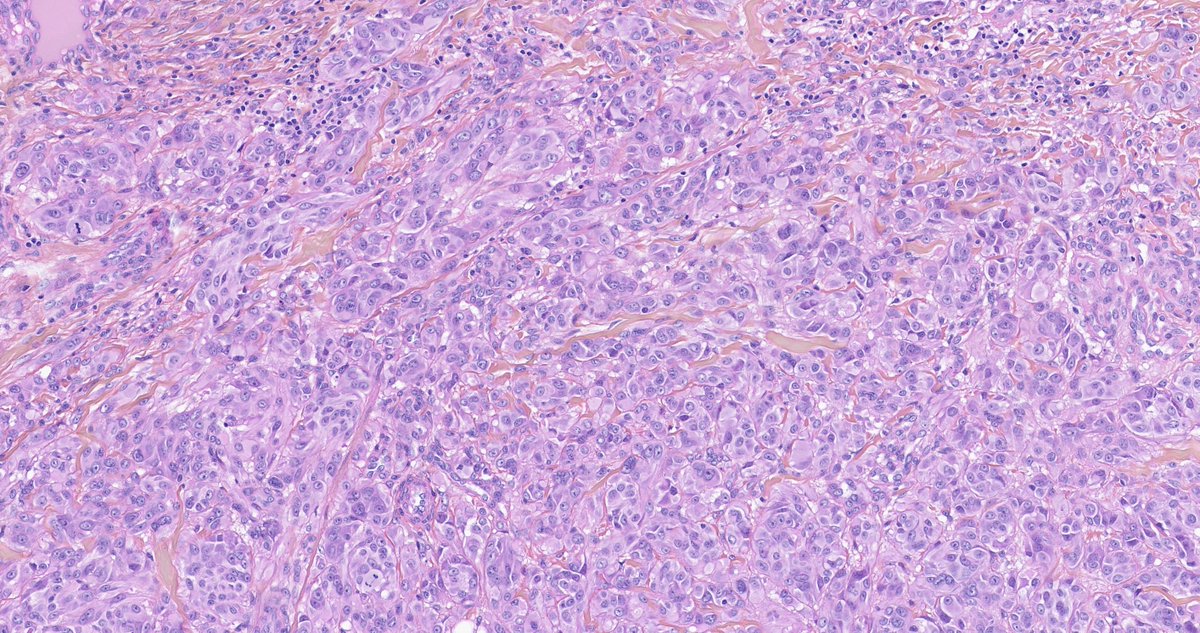

Spitz series 4/5 from the consult files of Arnaud de la Fouchardiere MD, PhD Multinucleated melanocytes, with moderate atypia, arranged in a sheet-like growth pattern in this MAP3K8-fused Spitz tumor #dermpath #dermatology

Spitz series 4/5 from the consult files of <a href="/melanopath/">Arnaud de la Fouchardiere MD, PhD</a>

Multinucleated melanocytes, with moderate atypia, arranged in a sheet-like growth pattern in this MAP3K8-fused Spitz tumor #dermpath #dermatology